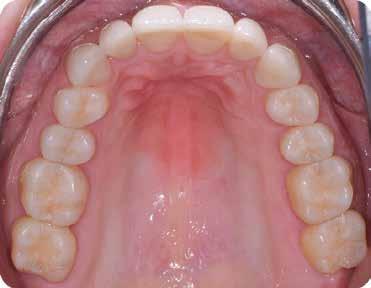

A 26 éves férfi páciens azzal a kéréssel kereste fel a rendelőnket, hogy a frontfogai esztétikusabb megjelenését szeretné elérni. A páciens jó általános egészségi állapottal rendelkezett, nem szenvedett allergiáktól és nem kellett rendszeresen gyógyszereket szednie. A páciens lehetőség szerint kerülte a fogai megmutatását. Rendkívül zavarónak találta a nagymetszői között, a középvonalnak megfelelően látható rést, a fogain látható kopási jeleket, valamint a fogai méretét is túl kicsinek találta. A szájüregi vizsgálat során megállapítottuk, hogy a nagymetsző fogai (11, 21) élharapásban vannak, valamint az alsó fogíven kismértékű torlódást észleltünk. A felső frontfogakon

(13-23) attrícióra utaló jeleket találtunk. A fogak kopása a nagymetszőfogaknak megfelelően volt a legkifejezettebb (1. ábra) . Az előbbiekben említett fogak (11, 21) ezen kívül némileg elfordultak, és jelentősebb méretű diasztéma volt köztük. A páciens Angle I.-osztályú állcsontrelációs helyzettel rendelkezett. A vizsgálat során feltűnt, hogy a páciens csak nagyon óvatosan mert mosolyogni (2. ábra)

A szájüregi vizsgálat során nem találtunk szuvas léziók jelenlétére utaló eltéréseket. A nagymetszőfogakon megfigyelhető jelentős mértékű kopás ellenére nem észleltünk craniomandibuláris diszfunkció jelenlétére utaló jeleket. A vizsgálat befejezését követően a pácienst tájékoztattuk a különböző kezelési lehetőségekről. Az esztétikai megjelenés javítása érdekében először egy alignerekkel végzett fogszabályzó kezelés elvégzését, majd a harapási helyzet optimalizálását követően a felső frontfogai kompozittal történő direkt felépítését vagy héjakkal történő ellátását (pl.: non-prep héjak) javasoltuk (3. és 4. ábra).

Az alignerekkel történő fogszabályzó kezelés elvégzéséhez az Invisalign rendszert használtuk. Az orthodonciai kezelés során 14 sín került felhasználásra. A páciensnek minden egyes sínt 10 napon keresztül kellett viselnie. A fogszabályzó kezelés céljai között szerepelt az élharapás megszüntetése, a szemfogak derotálása, valamint az alsó fogíven látható torlódás feloldása.

Az orthodonciai terápia során a fogív tágításra került, és a fogak között látható rések is egyenletes módon lettek elosztva a frontfogak között. Erre azért volt szükség, hogy a restauratív fázis során lehetőségünk legyen a harmonikus szé-

lességű és hosszúságú fogformák kialakítására (5. ábra)

A labiális és bukkális fogfelszínekre helyezett attachmentek feleltek a sínek által a fogakra kifejtett erők megfelelő átvitelének biztosításáért. Az eset ellátása során végzett orthodonciai előkezelést funkcionális szempontból a protetikai vagy restauratív célú fogászati beavatkozások közé sorolhatjuk. Ebben az esetben az orthodonciai beavatkozásnak az volt a célja, hogy lehetővé tegye a definitív fogpótlások minimálinvazív módon történő elkészítését. Az alignerekkel történő fogmozgatások befejezését követően a pácienst egy felső retenciós sínnel láttuk el. Az alsó fogíven az elért eredmények stabilitását fix retainer felhelyezésével biztosítottuk.

A fogazat minimálinvazív módon készített héjakkal történő ellátásához a fogaknak olyan pozícióban kell lenniük, amely lehetővé teszi az esztétikai megjelenés additív eljárások alkalmazása mellett történő optimalizálását.1. ábra: Kiindulási állapot. A felső nagymetszőfogak élharapásban vannak. 2. ábra: Az orthodonciai kezelés megkezdése előtt készített intraorális felvétel. A páciens csak óvatosan mer mosolyogni. 3. és 4. ábra: Digitálisan megtervezett kezelés.

A kezelések második fázisában a pácienssel közösen non-prep/ minimálinvazív héjak készítése mellett döntöttünk (6. és 7. ábra).

Az ilyen jellegű ellátás során csupán a lehető legkisebb mennyiségű foganyag kerül eltávolításra. A minimálinvazív beavatkozás elvégzését lehetővé tevő feltételeket a fogszabályzó kezelés során alakítottuk ki. A fogazat minimálinvazív módon készített héjakkal történő ellátásához a fogaknak olyan pozícióban kell lenniük, amely lehetővé teszi az esztétikai megjelenés additív eljárások alkalmazása mellett történő optimalizálását. Azonban az ellátás során előbbiekben felsoroltakon kívül más szempontokat is figyelembe kell vennünk. Amennyiben a páciens a jelenleg látható fogszínéhez képest jelentős változást szeretne elérni, úgy sokkal vastagabb héjak készítésére van szükség, és az ezáltal megnövekedett helyigény miatt sok esetben nincs lehetőség kizárólag additív eljárások alkalmazására (8. ábra). Mivel a cikkben bemutatásra kerülő eset ellátása során a fogazat helyzeti rendellenességei az előzetes orthodonciai kezelés keretei között korrekcióra kerültek, ezért lehetőségünk adódott a restauratív fázis minimálinvazív módon történő elvégzésére. Az általunk alkalmazott terápia hátrányai között szerepelt, hogy az elvégzett beavatkozások időigénye miatt a tervezett végeredményt csupán viszonylag hosszú idő után tudtuk elérni.

A páciens teljesen elégedett volt a kezelések befejezését követően elért esztétikai végeredménnyel (9. ábra). A terápiás erőfeszítéseink eredményeinek köszönhetően újra képes felszabadultan nevetni és mosolyogni. A cikkben bemutatásra kerülő eset jól példázza a multidiszciplináris beavatkozások alkalmazásában rejlő előnyöket. A megfelelő sorrendben végzett orthodonciai és restauratív kezelésekkel lehetővé vált a páciens mosolyának minimálinvazív módszerekkel történő optimalizálása. A körültekintő tervezésnek köszönhetően nem került sor felesleges beavatkozások elvégzésére, és emiatt a kezelések befejezéséhez szükséges idő sem nyúlt a szükségesnél hosszabbra. Arra is felhívnánk a figyelmet, hogy a jól megszervezett, továbbá a lehető legkevesebb rendelési időt felhasználó kezelések – a beavatkozásokat végző fogorvosok számára is – rendkívül kedvezőek lehetnek.